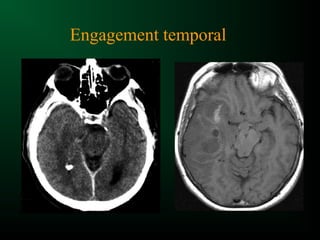

Engagements cérébraux

Effet de masse :

engagement sous falcoriel

Engagement sous-falcoriel

Engagement temporal

Engagement occipital